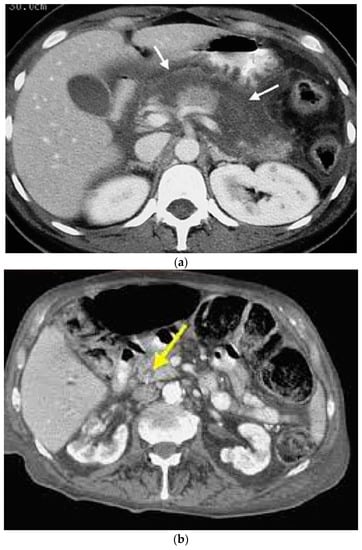

Complications

5. Diagnosis